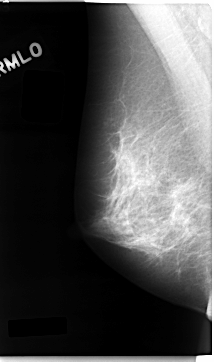

C_0026_1.RIGHT_MLO

RIGHT_MLO LINES 4696 PIXELS_PER_LINE 2776 BITS_PER_PIXEL 12 RESOLUTION 50 NON_OVERLAY